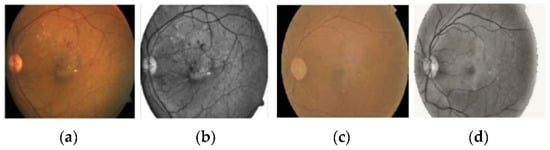

DR is an ocular impediment caused by diabetic disease; it has held its position as one of the main factors behind the occurrence of blindness globally [,,]. DR develops because of the long-standing occurrence of diabetes mellitus. The risks of disease are more common in patients with uncontrolled blood sugar. Generally, DR develops gradually and may not cause any symptoms or only mild vision loss in the primary stages. Eventually, if treatment and diagnosis are not performed in a timely manner, then it tends to cause blindness []. DR is generally categorized into three categories, normal, non-proliferative DR (NPDR), and proliferative DR (PDR), based on the progression of the diabetic retinopathy []. NPDR develops when new retinal blood vessels do not grow, and the blood vessel walls become faded. NPDR is divided further into mild, moderate, or severe stages of disease. In PDR, the retinal area is occupied by new blood vessels and obstructs the blood supply to the retina. Figure 1 shows samples of NPDR, PDR, and its subdivided classes of retinopathy discussed above [].

Figure 1. These images show the different types of retinopathies in the fundus images. (a) Normal, (b) mild, (c) moderate, (d) severe, and (e) proliferative.